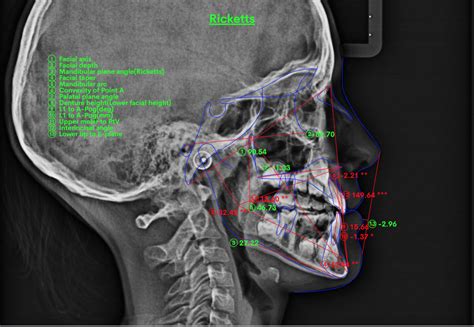

Una vez obtenidas las telerradiografias, se observa nítidamente la línea radiopaca que marca el borde anterior del masetero y que tomamos como referencia para medir los diferentes ángulos estudiados. Para el análisis cefalométrico se marcó el plano oclusal, el plano de Francfort, los ejes de los incisivos centrales superior e inferior, así como la perpendicular a la raíz distal del primer molar inferior con el fin de establecer su relación angular con el masetero y los planos estudiados (fig. 4).

Figura 4. Análisis cefalométrico.